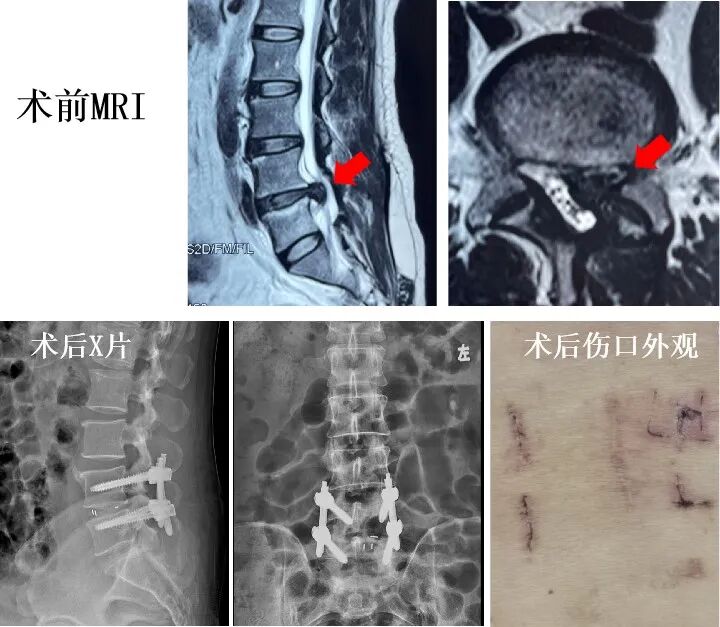

经过充分准备后,周治来副主任医师首先在张师傅背部开4个不到1厘米的切口,用脊柱内窥镜直视下完整摘除复发突出的髓核组织,彻底松解被压迫的神经根,并在透视下经皮置入椎弓根螺钉,历时2个多小时的手术顺利完成。

单侧双通道脊柱内镜(UBE)腰椎融合术是一种全新的、先进的术式,首先利用2个不到1厘米的切口,在生理盐水的持续冲洗下,全内镜可视化将压迫神经的椎间盘组织及黄韧带组织摘除,在内镜监视下植入融合器,最后经皮将椎弓根螺钉置入,既能做到双侧神经充分减压,又可以将软组织损伤降至最低,大幅缩短住院时间和康复周期。